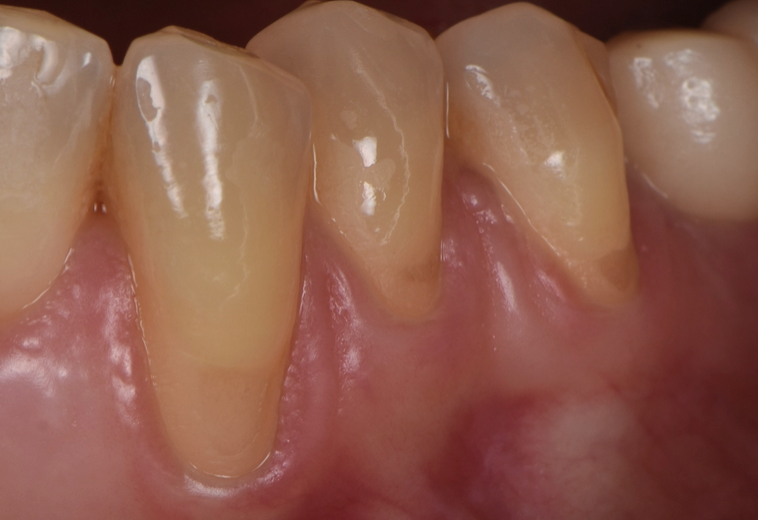

Una vez que hemos perdido encía y se ha quedado la raíz dental expuesta, podemos realizar cirugía mucogingival para volver a recuperar la estética y salud de nuestro periodonto.

Casos clínicos realizados por el Dr. Alfonso García

Antes

Caso 1